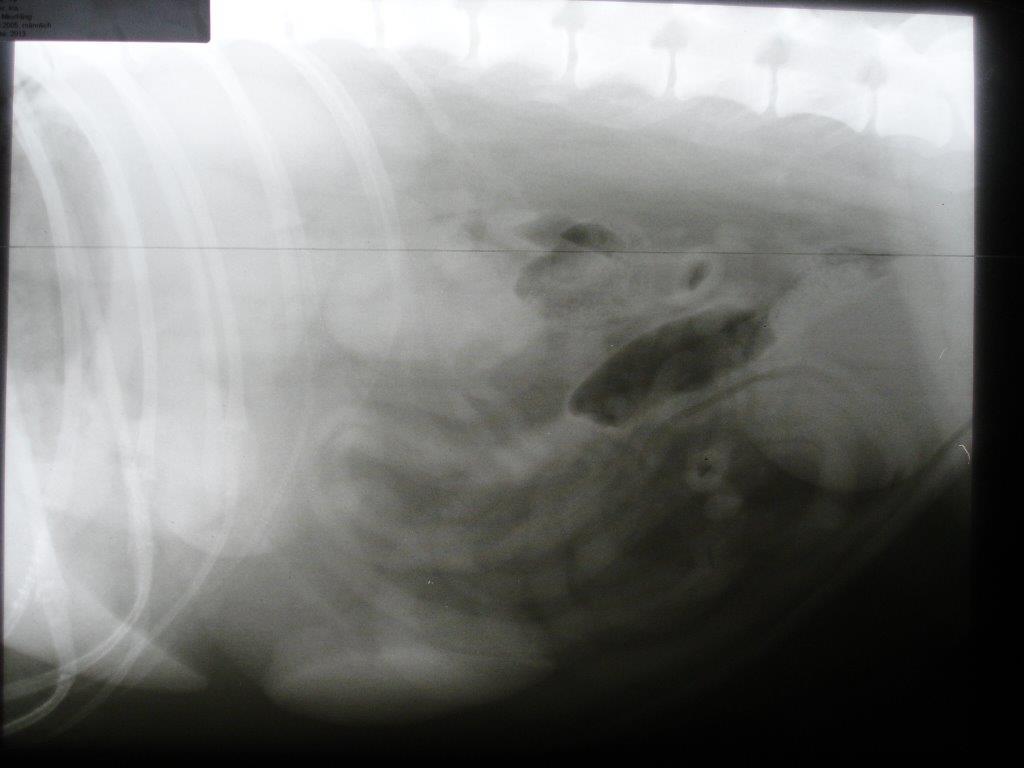

Die Analdrüsen und die äußerlich tastbaren Lymphknoten waren unauffällig. Daraufhin wurden Röntgenaufnahmen von Brust- und Bauchraum angefertigt. Im Brustkorb befand sich vor dem Herzen eine tennisballgroße Zubildung. Zur Diagnosestellung wurde dieser Tumor unter Ultraschallkontrolle mit einer Spritze punktiert und Zellmaterial gewonnen. Dieses Feinnadelaspirat wurde zu einem spezialisierten Tierpathologen geschickt. Der Befund: „Malignes Lymphom“. Das maligne Lymphom kann in einen B- und T-Zell-Typ eingeteilt werden, je nachdem welche Lymphozytenfraktion betroffen ist. In diesem Fall war es das schwieriger zu therapierende T-Zell-Lymphom. Die Ultraschalluntersuchung des Bauchraumes zeigte keine Veränderungen im Bereich von Leber, Milz und den anderen Lymphknoten des Bauches.

Bei Gino verschwand der erhöhte Durst bereits nach der ersten Medikamentengabe. Er wurde zusehends wieder fitter. Gelegentlich hatte er ein oder zwei Tage nach einer Chemo etwas weniger Appetit oder auch mal etwas Durchfall. Diese Beschwerden ließen sich aber durch die bereits im Vorfeld für das Eintreten solcher Fälle abgegebenen Medikamente gut bekämpfen. Der Tumor verschwand unter der Therapie vollständig. Nach 20 Wochen wurde die Therapie eingestellt. Leider kam der Tumor drei Monate später zurück. Die Symptomatik und Laborbefunde deckten sich mit denen vom Beginn der Erkrankung. Die Chemotherapie wurde nach dem gleichen Protokoll wieder gestartet. Nach dem 2. Zyklus verschlechterte sich sein Allgemeinzustand und die Ultraschalluntersuchung zeigte, dass der Tumor sich trotz der Therapie nun auch auf die Milz ausgebreitet hatte. Die Möglichkeit eines sogenannten Rescue-Protokolls mit einer Umstellung der Medikation auf bisher nicht verabreichte Chemotherapeutika wurde von der Besitzerin aufgrund der nun schlechten Prognose nicht mehr gewünscht. Gino wurde etwa ein Jahr nach Diagnosestellung eingeschläfert.